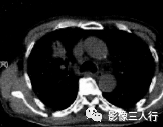

肺癌空气支气管征表现为结节内见到充气的支气管,常伴见分叶征、毛刺征、胸膜凹陷 征、空泡征。病理基础为一方面是癌细胞包围和浸润正常或异常的支气管,导致支气管出现 扭曲、扩张、变尖或中断,可为单支或多支,在走行方向上无一定的规律性;另一方面是支 气管近端癌性浸润或分泌物潴留成活瓣样通气的结果。肺癌的生长方式和肺支气管结构完整 与否是肺癌空气支气管征存在的决定性因素,据文献报道肺癌中出现空气支气管征的概率为 65%,且有此征象的肿瘤与无此征象的肿瘤相比,具有相对低度恶性的生物学行为。空气支 气管征多见于3cm以下的细支气管肺泡癌、腺癌、部分鱗癌及鳞腺混合癌。有资料显示, 直径<3mm的周围肺结节出现空气支气管征,是周围型肺癌特异性很高的征象,在肺癌诊 断中具有相当的价值。亦有资料显示,空气支气管征能进一步提示肺癌的组织类型,以腺癌 及肺泡癌多见,鳞癌相对少见,据统计,在肺癌内出现空气支气管征时,腺癌与肺泡癌的危 险度约3倍于鱗癌。见图11、图12。